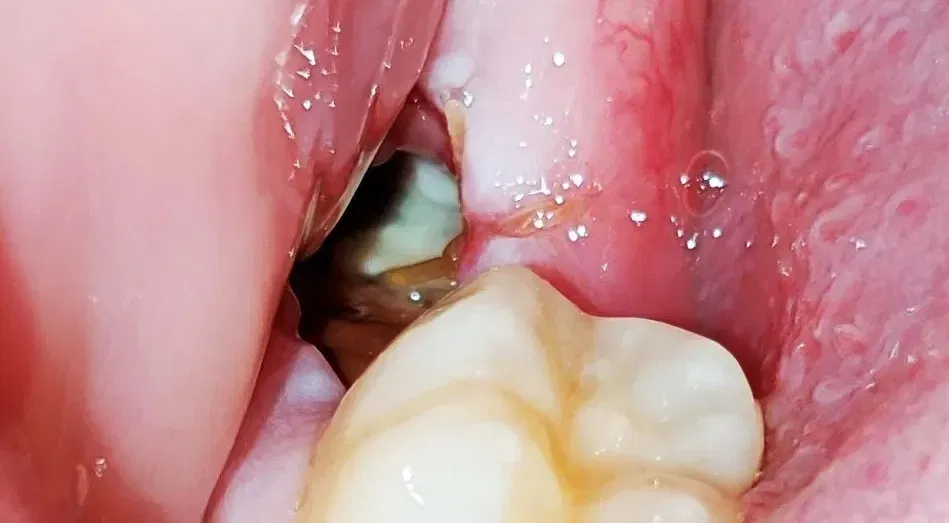

What Does a Normal Socket Look Like After Tooth Extraction?

Immediately following your tooth extraction, the socket will appear as a dark, blood-filled hole where your tooth once was. This is completely normal and expected. The area will be tender, and you may notice some bleeding for the first few hours. Within 24 hours, a dark red or brownish blood clot should form, covering the extraction site.

During the first week, the socket will gradually change appearance as healing progresses. The blood clot may appear whitish or yellowish on the surface—this is normal healing tissue, not infection. The surrounding gum tissue may be slightly swollen and sensitive to touch.

Visual Appearance: A normally healing socket will have a dark blood clot visible initially, then gradually fill with pinkish-white granulation tissue. The socket with dry socket appears empty—you can often see exposed bone at the bottom, which may appear grayish-white or yellowish. The surrounding gum tissue may look inflamed.